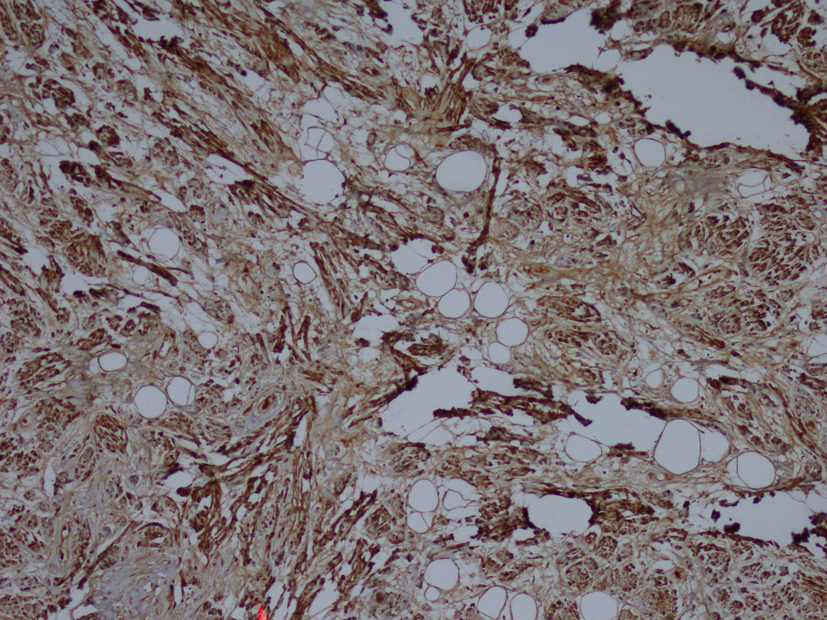

Macroscopic examination of the radical nephrectomy material measuring 18 × 7 × 5 cm showed a solid, gray-white colored tumor measuring 10 × 7 × 3 cm, located in the upper pole of the kidney but without any direct relation to the kidney. Focal adrenal tissue was observed in the cross-section of the tumor. The kidney and surgical margins were tumor-free. Three lymph nodes measuring 1 cm in diameter were detected in the renal hilus. The microscopic examination revealed mature ganglion cells in Schwannian stroma. The immunohistochemical examination showed strong positive staining for S100, neuron-specific enolase, synaptophysin and chromogranin. These three lymph nodes are considered to be reactive lymph nodes (Fig. 1-3).

![]() Click for large image | Figure 3. Immunohistochemistry showing S100 (× 100). |